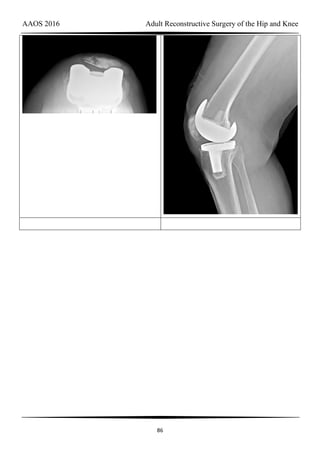

Figure 36a Figure 36b

Question 36 of 200

Figures 36a and 36b are the radiographs of a 79-year-old woman who has been

experiencing increasing tibial pain 10 years after undergoing revision total knee arthroplasty.

There is no evidence of infection. What is the most appropriate treatment?

1- Retain the components and implant a tibial strut allograft

2- Revise the tibial component with a metaphyseal cone and metaphyseal uncemented stem

3- Revise the tibial component with a metaphyseal cone and a press-fit diaphyseal-

engaging stem

4- Revise the tibial component with a long cemented diaphyseal-engaging stem

PREFERRED RESPONSE: 3- Revise the tibial component with a metaphyseal cone and

a press-fit diaphyseal-engaging stem

DISCUSSION

Stems are available for cemented and press-fit implantation. To be effective, press-fit

stems should engage the diaphysis (Figures 36c and 36d). They also assist in obtaining correct

limb alignment. Short metaphyseal-engaging stems are associated with failure rates between

AAOS 2016 Adult Reconstructive Surgery of the Hip and Knee

31

16% and 29%. Cemented stems may be shorter than press-fit stems because they do not have

to engage the diaphysis. Short, fully cemented stems offer the advantage of metaphyseal

fixation. Hybrid stem fixation makes use of the metaphysis for cement fixation with

metaphyseal cones or sleeves and diaphyseal-engaging press-fit stems.